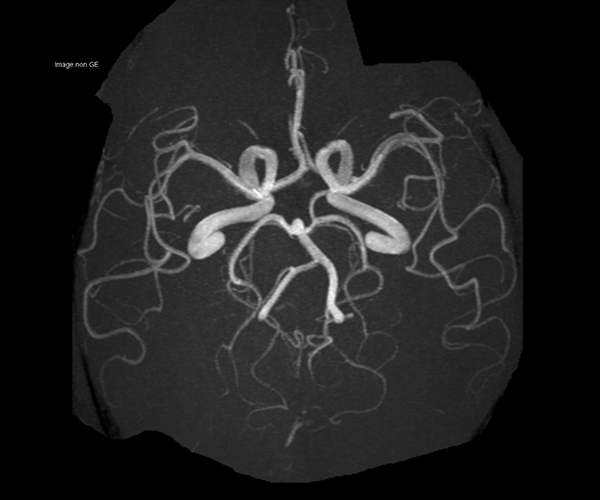

L’augmentation de l’effet de susceptibilité magnétique à plus haut champ permet d’améliorer la détection des hémorragies et est utilisé également dans l’imagerie de perfusion (tumeurs) et l’IRM fonctionnelle (BOLD). L’allongement du T1 à plus haut champ entraîne une meilleure saturation des tissus statiques et par conséquent une augmentation du contraste sang/tissus dans l’AngioIRM.

Une IRM 3T permet d’augmenter l’intensité du champ magnétique, ce qui entraîne une augmentation proportionnelle du rapport signal/bruit et permet donc une augmentation du signal IRM. Cette augmentation de signal peut être exploitée de différentes manières et avoir plusieurs avantages : par exemple raccourcir le temps de l’examen avec un signal équivalent à celui d’un champ magnétique standard ; pour la même durée d’examen, permettre de choisir plus de résolution spatiale pour affiner l’analyse de petites structures ou d’anomalies ; ou encore explorer dans de meilleures conditions un phénomène dynamique, par exemple la vascularisation cérébrale.